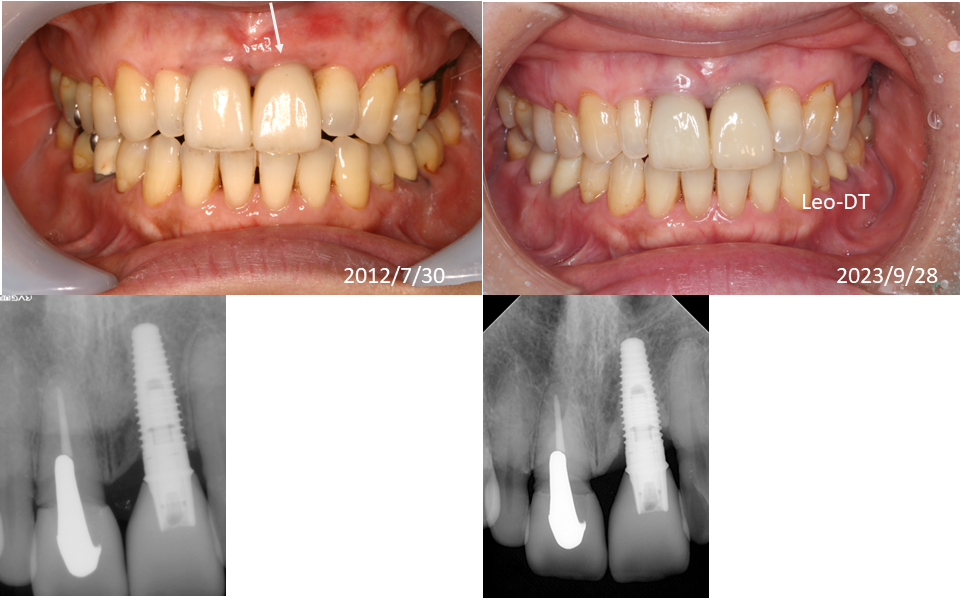

症例集

天然の歯と同様の機能と審美性